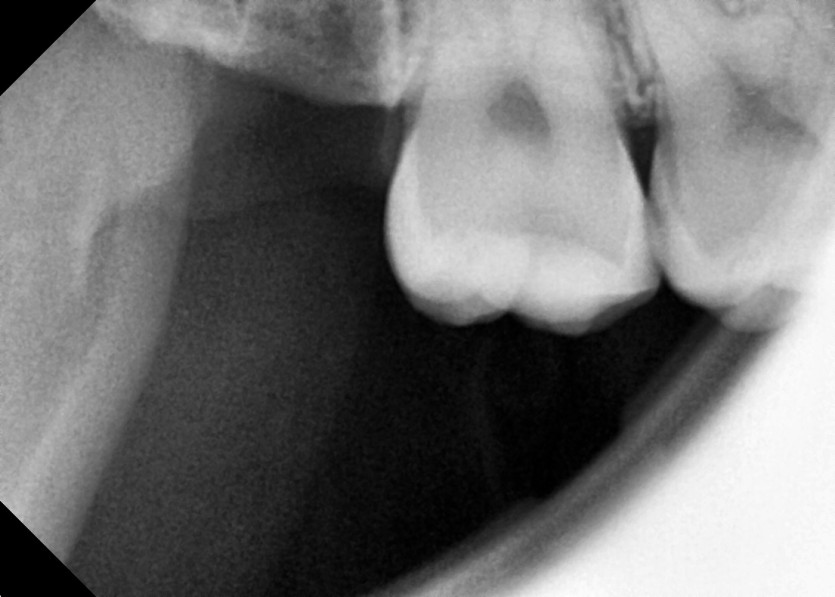

#18,48 사랑니 발치

구강 외과 전문의가 당일 발치했습니다.